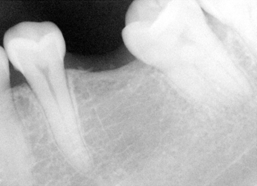

Dental history: #9 fracture at age of 8; #9,10 crowns (joined) 2 years ago; #9 has chronic apical infection, #19 extracted due to caries at age of 15

Remove #9,10 crowns, #9 lingual margin subgingival; pulpal test: #8,10 necrosis. Remove #9 post, redo RCT, #8, 10 RCT, #8,10 in office internal bleaching; #9 cast post, ortho extrusion before #9,10 crowns